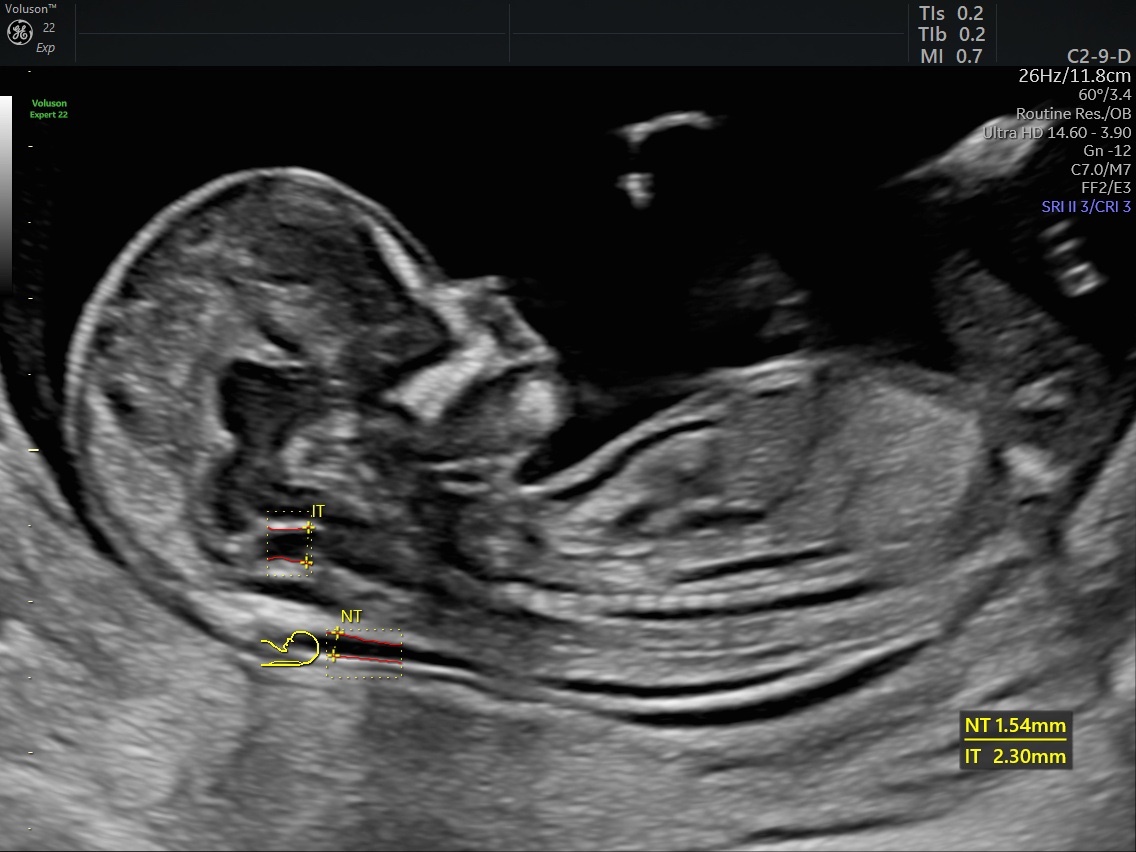

Ο κατάλληλος χρόνος για την εξέταση της αυχενικής διαφάνειας είναι μεταξύ της 11ης και 14ης εβδομάδας.

Είναι το υπερηχογράφημα κατά το οποίο γίνεται η μέτρηση της αυχενικής διαφάνειας του εμβρύου (Nuchal Translucency – NT).

Ταυτόχρονα, γίνονται και άλλες υπερηχογραφικές μετρήσεις που περιλαμβάνουν την παρουσία ή όχι του ρινικού οστού, τη ροή του αίματος στην τριγλώχινα βαλβίδα, τη ροή του αίματος στο φλεβώδη πόρο και τη καρδιακή συχνότητα.

Η αυχενική διαφάνεια σε συνδυασμό με τους βιοχημικούς δείκτες free-βhcG και PAPP-A μπορεί να υπολογίσει με υψηλή ακρίβεια την πιθανότητα για σύνδρομο Down αλλά και για κάποιες άλλες χρωμοσωμικές ανωμαλίες.